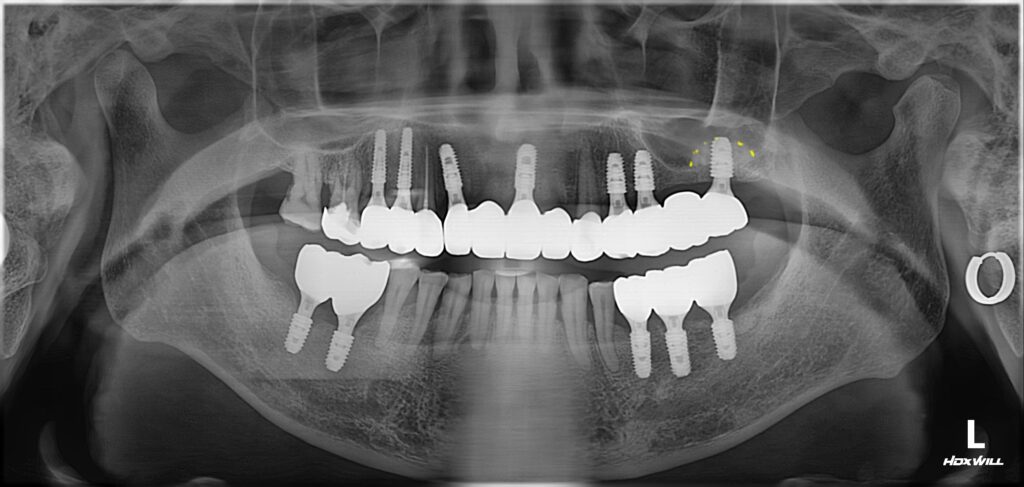

위 환자분은 다수의 어금니와 상악 전치부(위턱 앞니)를 모두 발치하고 임플란트를 식립하였습니다.

임플란트 심어진 것을 보시면 알겠지만 굉장히 보기가 좋게 심어졌죠? 보기 좋은 임플란트가 기능도 좋습니다.^^

저렇게 반듯하게 그리고 이상적인 간격으로 임플란트를 심어야 임플란트 완성 후 장기간 동안 건강하게 유지될 수 있습니다.

어금니에는 ‘상악동 거상술’을 통해서 뼈이식 임플란트를 완성했는데 ‘상악동 거상술’에 대해서는 아래 글을 참고해 주세요.

다행히 다른 부위는 뼈 상태가 좋아서 따로 뼈이식을 하지는 않았습니다.